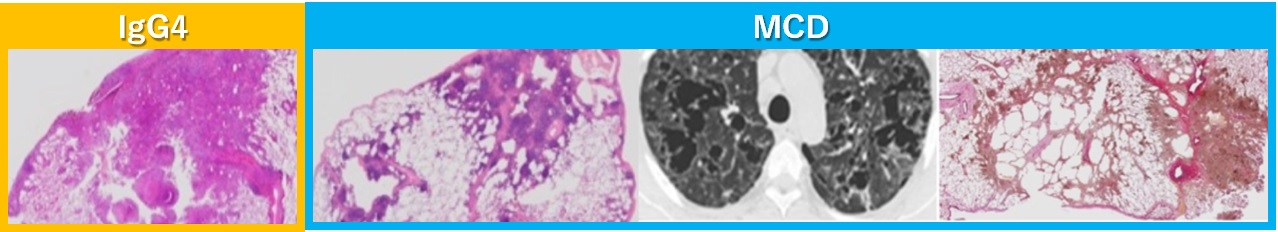

リンパ球増殖性肺病変は、IgG4やMulticentric Castleman’s Disease(MCD)の肺病変、膠原病肺、薬剤性肺障害など多彩で、症例数も増え、予後も違い、その診断の鑑別と治療は今後ますます問題となってきています。私たちは、様々なリンパ球浸潤性肺疾患についての研究を症例やモデルを使って行っています10-13。その中でも鑑別が問題となる、IgG4とMCDの肺病変を東京びまん性肺疾患研究会を通じ、全国レベルで症例を集積し病理学的に解析してきました。両者は、共に気管支血管周囲など広義間質中心のリンパ球増殖性病変でしたが、IgG4は広義間質自身の幼若な線維化で、MCDでは成熟した硝子線維化が中心で嚢胞化が目立つという違いを報告しました14-17。この報告はIgG4肺病変の診断基準の元になる重要な研究でしたが15,18,19、リンパ球浸潤所見は共通でも、線維化タイプや嚢胞化などベクトルが大きく違う病変の理由はまだ明らかではありません。

この2種の病変の肺局所のリンパ球、形質細胞の性質自体に大きな違いがあり、これを調べると病態の違いが分かりやすいのでないかと仮説を立てています。これを実施する希少なヒト検体を保有しており、この病変からのリンパ球自身を病理ならではのマイクロダイセクション法でピンポントでサンプリングする手法を用い、蛋白、遺伝子の網羅的な解析を行い、病態関連因子を抽出し、動物モデルも応用してバイオマーカーとして開発、治療応用を目指す研究を展開しています。多様なリンパ球浸潤性病変の病態解明の突破口になり得る研究であり、広く肺の線維化や嚢胞化の病態解明にも繋がる研究でもあります。